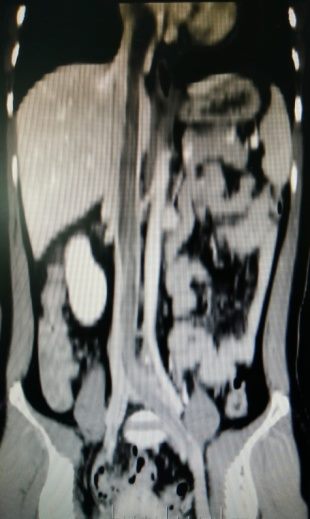

患者到郑州大学五附院查彩超提示心脏、下腔静脉及髂静脉巨大肿物,后行CTV检查确诊。充分准备后,郑州大学五附院王兵副院长、血管外科崔文军教授带领团队精心施术,胸外科高兴才主任和麻醉科胡强夫主任一同为病人保驾护航,做好随时开胸手术的准备。幸运的是腹部切口就完整取出了完整肿物。术后患者病情平稳,头晕心慌症状消失,病理确诊平滑肌瘤。此类手术的完成标志医院在复杂罕见血管疾病的诊治再上一台阶。

▲ 下腔静脉CTV提示瘤体蔓延至心脏